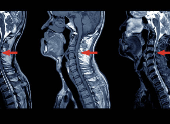

목디스크는 의학적으로 ‘경추 추간판 탈출증’이라고 하는데요. 경추(목뼈) 사이에서 쿠션 역할을 하는 디스크가 외부 충격이나 잘못된 자세, 퇴행성 변화로 인해 밀려나오면서 신경을 압박하여 통증과 불편을 유발하는 질환이에요. 특히 20~40대 젊은 층에서도 자주 발생하고 있어 각별한 주의가 필요하답니다.

이 경우 MRI나 X-ray 등의 정밀 검사를 통해 상태를 정확히 확인할 필요가 있습니다.